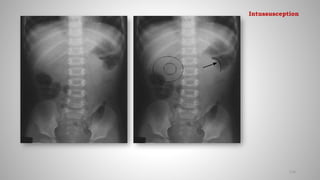

• Meniscus sign: Crescent of gas within colonic lumen that outlines the

apex of intussusceptum

Meniscus sign